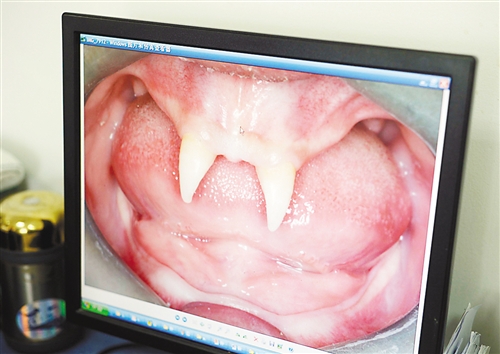

12月18日,16歲的張成(化名)從小到大,只有上顎部分有兩顆牙,看上去更像長著一對(duì)獠牙。 記者熊明攝

重慶日?qǐng)?bào)訊 每個(gè)人都有牙齒,但對(duì)16歲的張成(化名)來說,從小到大,他只有上顎部分有兩顆牙,看上去更像長著一對(duì)獠牙,這讓他很自卑又易怒。12月18日,在母親的陪同下,他來到三軍醫(yī)大西南醫(yī)院求助。經(jīng)醫(yī)生檢查,發(fā)現(xiàn)張成患有一種罕見的基因病。

張成是貴州銅仁地區(qū)思南縣人,從生下來就似乎得了一種怪病,身上毛發(fā)稀少,面部發(fā)育也不好。更奇怪的是,別人家的孩子都長牙吃東西了,他卻一直長不出牙齒,最后只在上顎部分冒出兩顆比較突出且對(duì)稱的牙齒,看起來就像一對(duì)獠牙。

在母親陪同下,張成來到西南醫(yī)院口腔頜面外科就診。經(jīng)醫(yī)生檢查,張成被確診為無汗型外胚層發(fā)育不良。

據(jù)介紹,該病的發(fā)病率不到十萬分之一,是一種較為罕見和嚴(yán)重的基因病,多見于男性。如果患上這種病,其乳牙或恒牙會(huì)先天性缺失,還可能伴隨淚腺發(fā)育障礙、視光敏感、視力下降、聽力障礙、唇腭裂、發(fā)音困難、身材矮小、乳房發(fā)育不良等癥狀。以西南醫(yī)院為例,每年都會(huì)遇見一兩例這樣的患者,但像張成這樣嚴(yán)重的,非常少見。